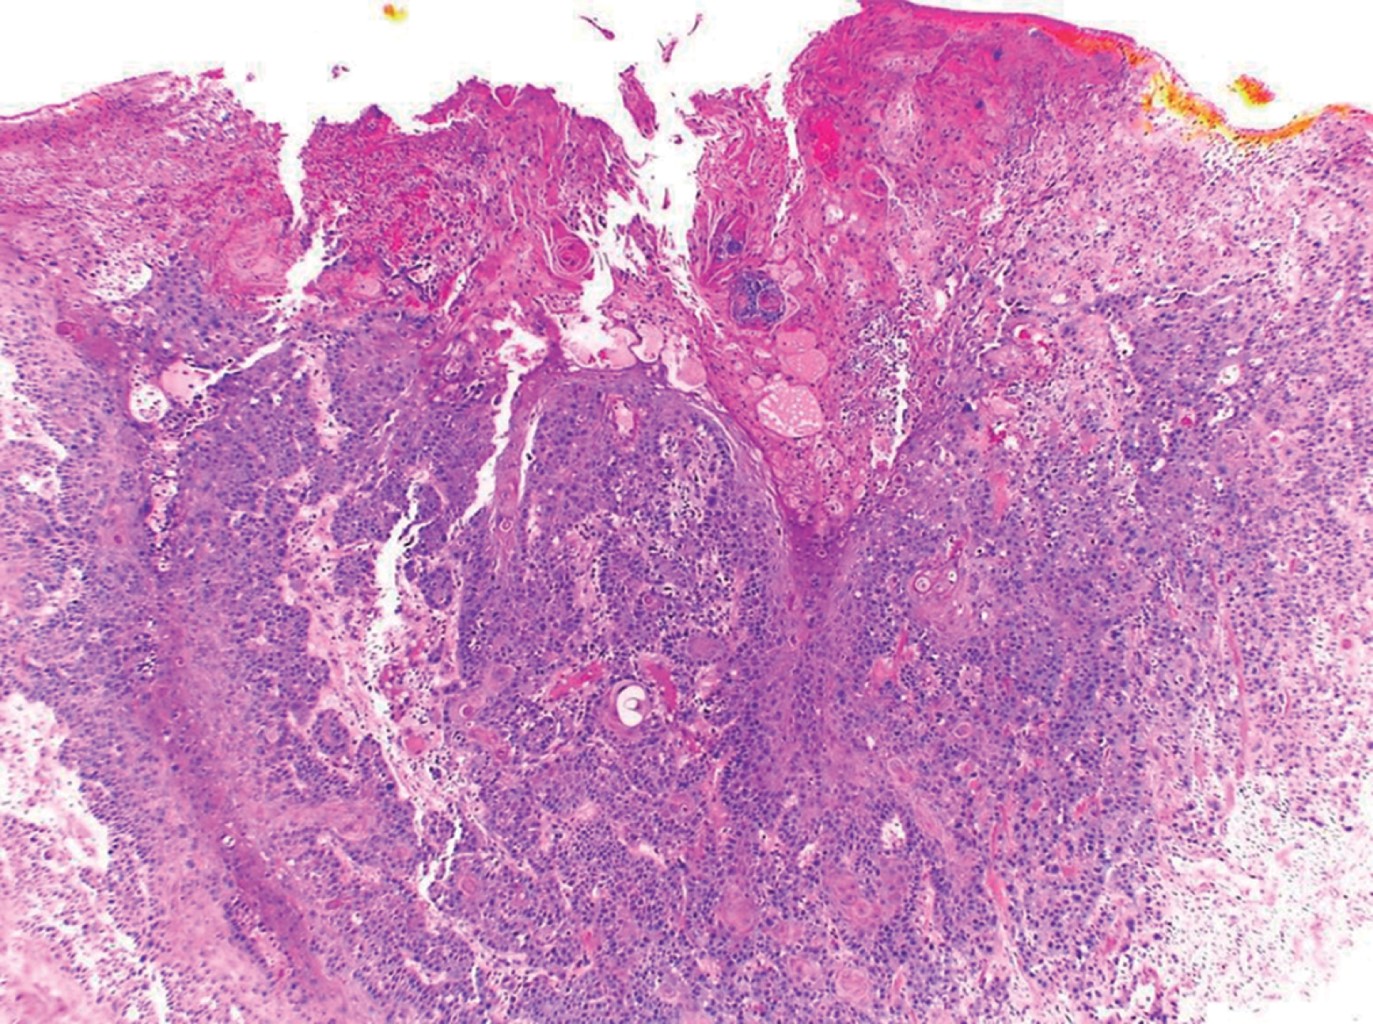

HISTOPATOLOGíA

Las imágenes histopatológicas muestran patrones de diferentes carcinomas cutáneos, principalmente de carcinoma epidermoide en 71%.3 El resto corresponde a carcinoma basocelular, melanoma, sarcoma, entre otros.1,3

Paciente del sexo masculino, de 43 años de edad, originario y residente de Guerrero, desempleado. Acude por una dermatosis localizada a tronco, del que afectaba tórax posterior en la región escapular izquierda; constituida por una neoformación exofítica, de 10 × 8 cm en su eje mayor, ulcerada, con costras melicéricas y secreción purulenta en su superficie, de bordes irregulares y bien definidos (Figura 1). Presentaba también una segunda neoformación en región escapular y hombro de lado izquierdo, de aspecto atrófico, de 9 cm de diámetro, con escama amarillenta y gruesa en su superficie, de bordes mal definidos (Figura 2), ambas de evolución crónica, dolorosas, que emitían olor fétido. Presentaba además adenopatías palpables ipsilaterales. Como antecedentes de importancia refirió haber sufrido una quemadura de tercer grado extensa en tórax y extremidades superiores con gasolina 22 años antes. El padecimiento actual lo inició hace tres años, con una "bola de rápido crecimiento" (sic paciente), la cual más tarde se ulceró en forma espontánea, acompañándose de sangrado y dolor progresivo. Acudió con especialista en Guerrero quien realizó biopsia y lo canalizó a este centro dermatológico con el diagnóstico de carcinoma epidermoide moderadamente diferenciado queratinizante, invasor (Figuras 3, 4 y 5). Al tratarse de un tumor de alto riesgo, el paciente fue referido a un hospital de tercer nivel en donde falleció al mes del internamiento debido a choque séptico y fascitis necrotizante.

Figura 3